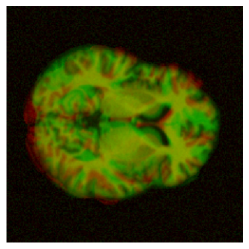

|

pre-aligned |

![]() |

|---|---|---|---|

large deformation |

| before registration | SVF | (ours) |

To motivate our work, consider the example in Fig. 1, in which we performed a 3D registration of two MRI brain scans from the OASIS [7] dataset using the popular Stationary Velocity Field (SVF) approach [8, 9, 10] and our proposed method (denoted ). In the first example, the sought deformation is comparably small before the registration process, and both approaches perform equally well. In the second example, the deformation includes a larger rotational component. When looking at the deformed images only, the SVF approach appears to generate an alignment that is clearly worse, but not catastrophically so. This is deceptive: inspecting the generated deformation fields (Fig. 2), it becomes clear that the SVF approach generates a deformation that – while it maps corresponding intensity values reasonably well between the images – is far from the ground truth.

This behavior is clearly visible in Fig. 1 and Fig. 2 shown in the introduction, in which the resultant images as well as an exemplary slice of the deformation field are depicted under small and large deformations. It illustrates how the matrix group approach is able to capture even large rotational deformations, whereas the use of an SVF tends to align the intensity values by local deformations instead of a global rotation, resulting in the large RMSE observed in Fig. 12.